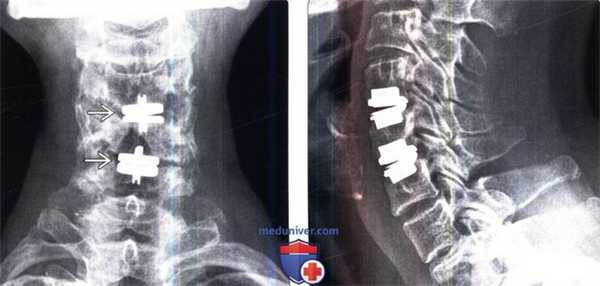

(Слева) Рентгенография шейного отдела позвоночника в прямой проекции: протезы дисков ProDisc-C на двух уровнях . Подобные вмешательства позволяют сохранить практически нормальную подвижность обоих оперированных сегментов и не приводят к ограничению подвижности смежных сегментов. Это дает основания полагать, что подобные многоуровневые ТЗШД могут быть более предпочтительными, чем спондилодезы.

(Справа) Рентгенография в боковой проекции после двухуровневого ТЗШД протезами ProDisc-С. Эти полусвязанные металл-полиэтиленовые протезы позволяют сохранить подвижность оперированного сегмента, высоту соответствующих межпозвонковых отверстий и сагиттальный баланс позвоночника. Ротационная подвижность между компонентами протеза в ряде случаев может приводить к биомеханической перегрузке дугоотростчатых суставов.